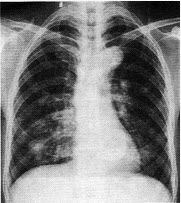

�����У�74�ꡣ��������������4���£�MRͼ�����£����п��ܵ�����ǣ���

A.ǰ��������

B.ǰ���ٰ�

C.ǰ��������

D.���װ�

E.����ǰ������